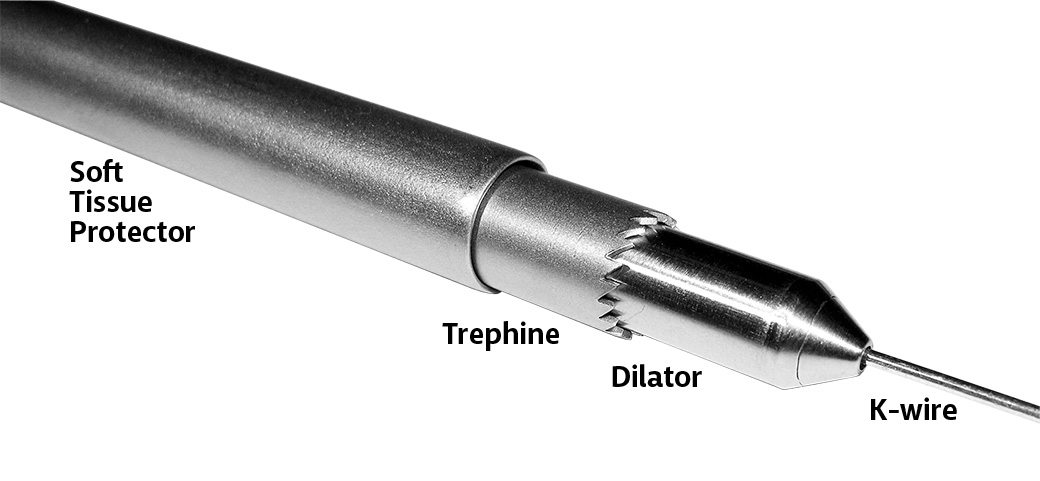

Cannulated T-handle and trephines allow use of a standard 1.6 mm (.062″) threaded K-wire to help facilitate grasping and removal of a core bone sample for biopsy or core decompression

- • Allows use of trephine at oblique angles to bone surface by using an anchoring K-wire and cannulated trephine

- • Avoids “skipping” of trephine teeth on bone surface

- • Facilitates optimal approach angle and direction of trephine

- • Minimally invasive — soft tissue sleeve protects surrounding structures and tissue